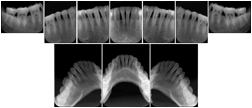

Intra-oral radiography typically involves acquisition of multiple images of various parts of the dentition. Many digital radiographic systems offer customized templates that are used for displaying the images in a study on the screen. These templates may also be referred to as mounts or view sets. The Structured Display Object represents a standard method of encoding and exchanging the layout and intended display of Structured Displays. A structured display object created in this manner could be stored with a study and exchanged with images to allow for complete reproduction of the original exam.

1. A patient visits a General Dentist where a Full Mouth Series Exam with 18 images is acquired. The dentist observes severe bone loss and refers the patient to a Periodontist. The 18 images from the Full Mouth Series along with a Structured Display are copied to a DICOM Interchange CD and sent with the patient to see the specialist. The Periodontist uses the CD to open the exam in his Dental Radiographic Software and consults via phone with the General Dentist. Both are able to observe the same exam showing the images on each user's display using the exact same layout.

Intra-oral Full Mouth Series Structured Display

Figure OO-1. Intra-oral Full Mouth Series Structured Display